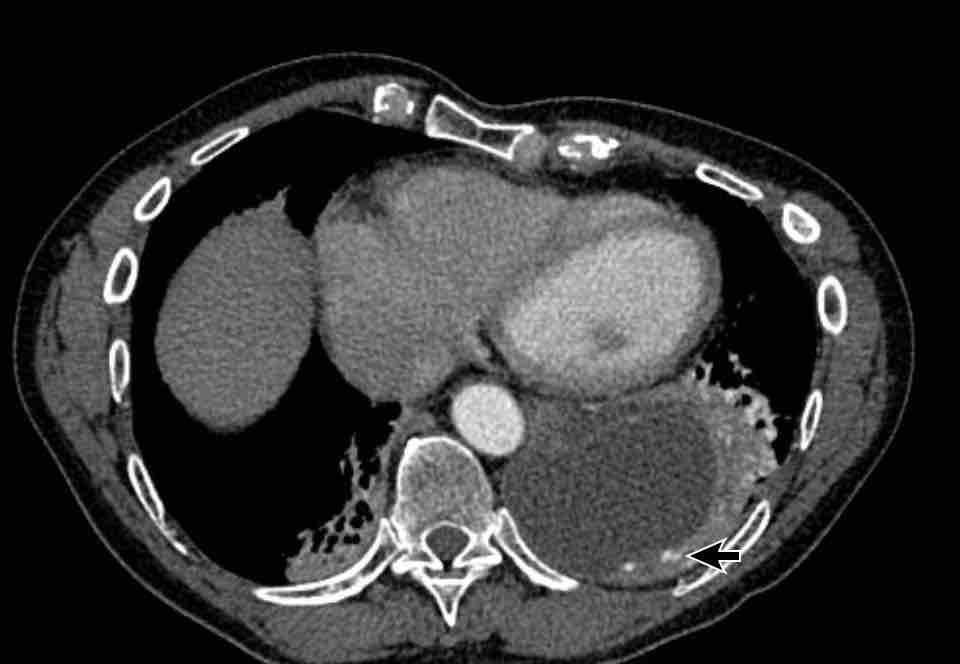

Hình ảnh

Phì đại động mạch phế quản với đường kính lên đến 4 mm (mũi tên) kèm theo một túi phình nhỏ (đầu mũi tên).